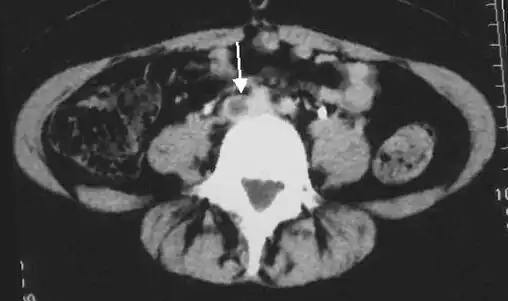

An abdominal CT scan demonstrating an iliofemoral DVT, with the clot in the right common iliac vein of the pelvis

CT scan venography, MRI venography, or a non-contrast MRI are also diagnostic possibilities.[120] The gold standard for judging imaging methods is contrast venography, which involves injecting a peripheral vein of the affected limb with a contrast agent and taking X-rays, to reveal whether the venous supply has been obstructed. Because of its cost, invasiveness, availability, and other limitations, this test is rarely performed.[39]